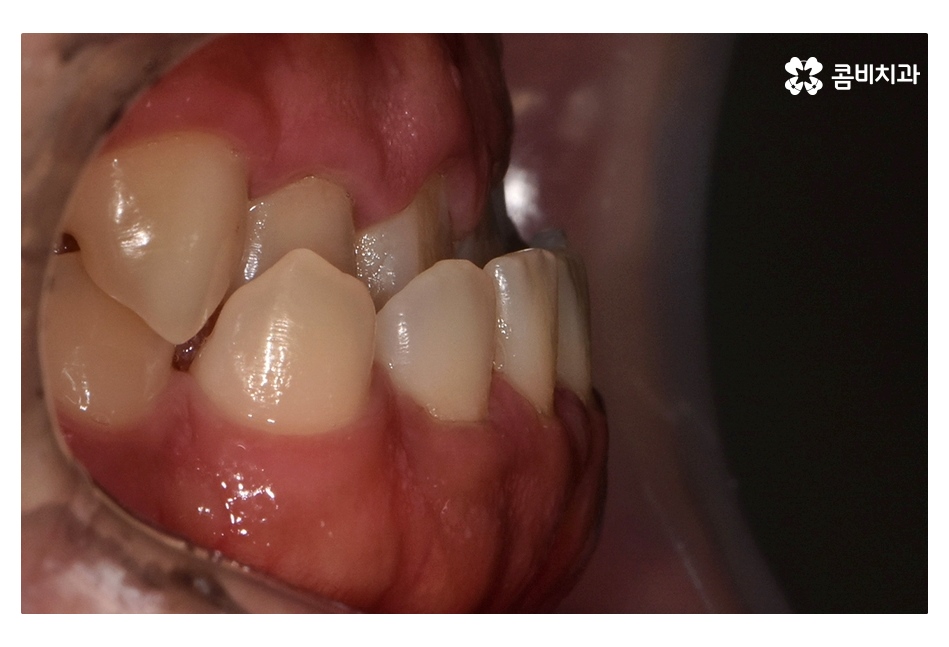

클리피씨교정이 진행되고 시간이 지날수록 아랫니가

점점 윗니에 덮이는 정상 교합의 상태로 개선되는 것을 볼 수 있는데요.

부정교합은 증상에 따라 심할경우 평생 식사를 할 때마다 불편함을 느낄 수도

있지만 치아교정을 통해 치료를 하면 치아의 심미성은 물론이며

발음, 턱관절 등 건강에도 큰 이점을 줄 수 있어요.